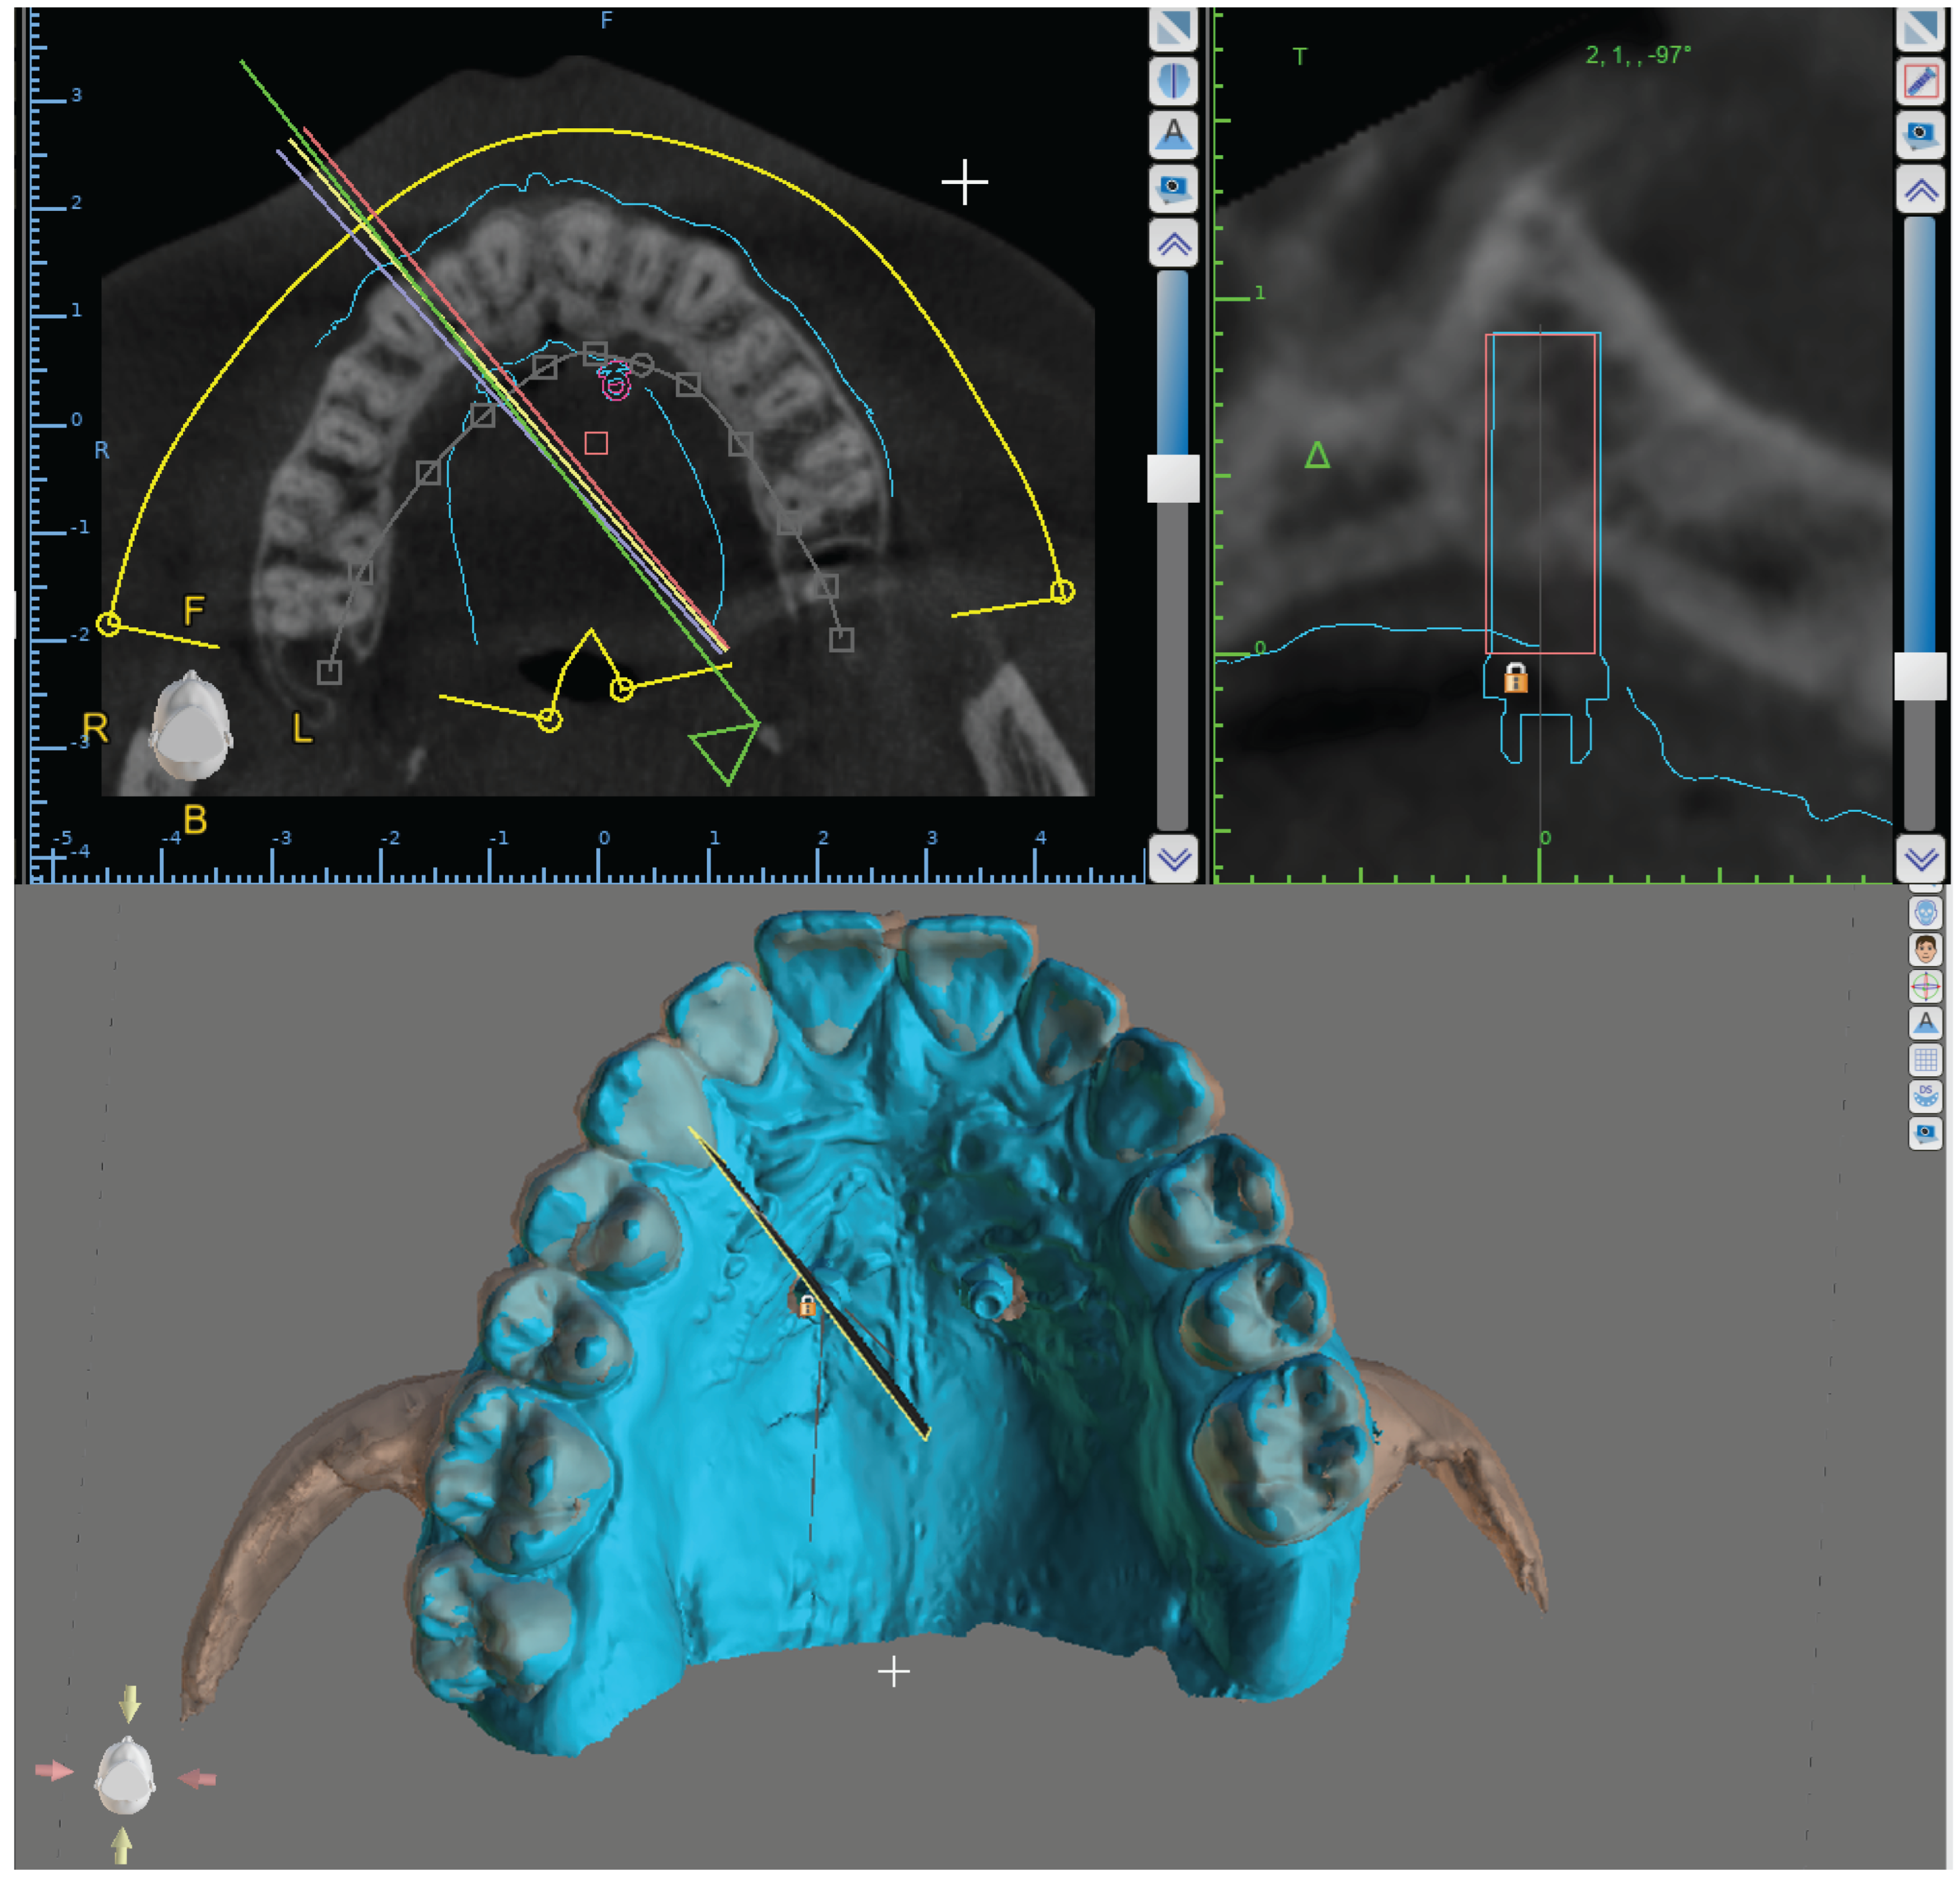

DICOM files and maxillary digital model have been imported into a specific software used for planning 3-dimensionally miniscrew position (BlueSkyPlan software version 4.7, Blue Sky Bio, LLC, Grayslake, IL, USA).

Subsequently, Blue Sky Plan software was used to superimpose maxillary digital models and CBCT volumes (Figure 1). The software (internationally registered as a medical device) used an algorithm to automatically superimpose the digital maxillary model and the CBCT volume scan. Blue Sky Plan software was also used to design the surgical guide.

Figure 1. Blusky Plan Software interface, overlaying digital maxillary models and CBCT volumes.